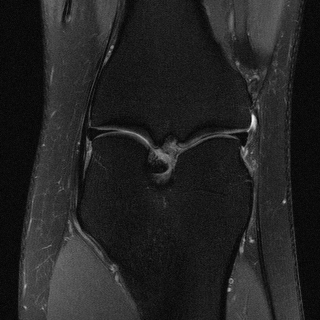

This article presents a novel undersampled magnetic resonance imaging (MRI) technique that leverages the concept of Neural Radiance Field (NeRF). With radial undersampling, the corresponding imaging problem can be reformulated into an image modeling task from sparse-view rendered data; therefore, a high dimensional MR image is obtainable from undersampled $k$-space data by taking advantage of implicit neural representation. A multi-layer perceptron, which is designed to output an image intensity from a spatial coordinate, learns the MR physics-driven rendering relation between given measurement data and desired image. Effective undersampling strategies for high-quality neural representation are investigated. The proposed method serves two benefits: (i) The learning is based fully on single undersampled $k$-space data, not a bunch of measured data and target image sets. It can be used potentially for diagnostic MR imaging, such as fetal MRI, where data acquisition is relatively rare or limited against diversity of clinical images while undersampled reconstruction is highly demanded. (ii) A reconstructed MR image is a scan-specific representation highly adaptive to the given $k$-space measurement. Numerous experiments validate the feasibility and capability of the proposed approach.